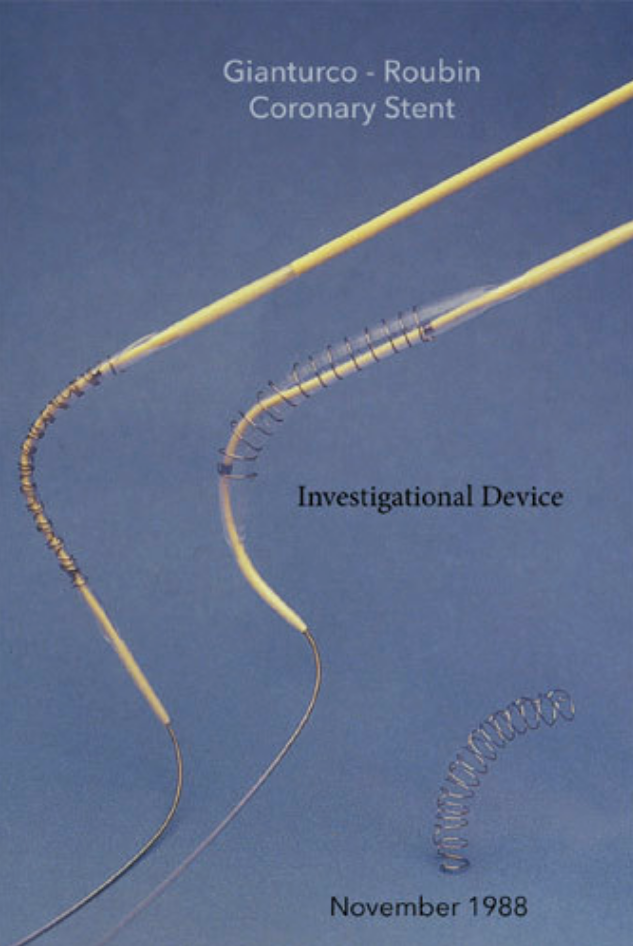

The First Balloon-Expandable Coronary Stent - An Expedition That Changed Cardiovascular Medicine - A Memoir - by Gary Roubin - 2015

![“ We performed the first coronary angioplasty [at UAB] in 1982, and the technology raced ahead in the years to follow. Particularly important was the development of the stent, a tiny spring ‘like that in your ball-point pen, only a bit larger,’ p](https://images.squarespace-cdn.com/content/v1/522b22f2e4b04879e6b51037/1596998467392-T37YI1NAKLYGVW2T44Z3/Screen+Shot+2020-08-09+at+1.39.09+PM.png)

![“ We performed the first coronary angioplasty [ at UAB] in 1982, and the technology raced ahead in the years to follow. Particularly important was the development of the stent, a tiny spring ‘like that in your ball-point pen, only a bit large](https://images.squarespace-cdn.com/content/v1/522b22f2e4b04879e6b51037/1596755620909-1HRJBE6NLW8ZE6LCKP1P/IMG-7986.jpg)